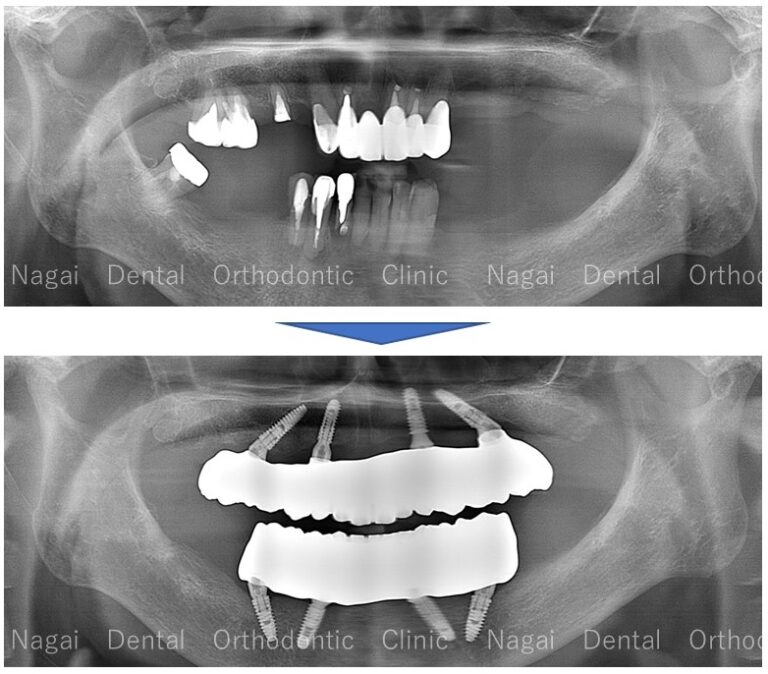

【口腔内の詳細変化】

▲一部の歯に集中していた負担を軽減し、全体的な咬合バランスの改善を図りました

▲取り外しの不要な固定式補綴物により、咀嚼機能の回復を目指しました

| 治療内容 | 上顎:オールオンフォー(ジルコニアセラミック仕上げ)※5本のインプラントを使用 |

| 年齢/性別 | 60代/女性 |

| 背景 | 上顎前歯の被せ物(差し歯)と下顎臼歯部のブリッジが外れたことを主訴に来院されました。下顎の奥歯は虫歯が進行して歯根のみの状態となっており、噛み合わせの支持が失われていたため、上顎の前歯部に過度な負担がかかっている状態でした。 |

| 治療期間 | 12か月(通院14回) |

| 費用 | 上顎:3,141,600円 |

| リスク/副作用 | インプラント手術は、ご高齢の方や全身状態(持病など)によっては適応とならない場合があります。また、術後の清掃を怠ると天然歯の歯周病に似たインプラント周囲炎が起こる可能性があるため、ご自宅でのセルフケアと定期的なメンテナンスが必要です。 |